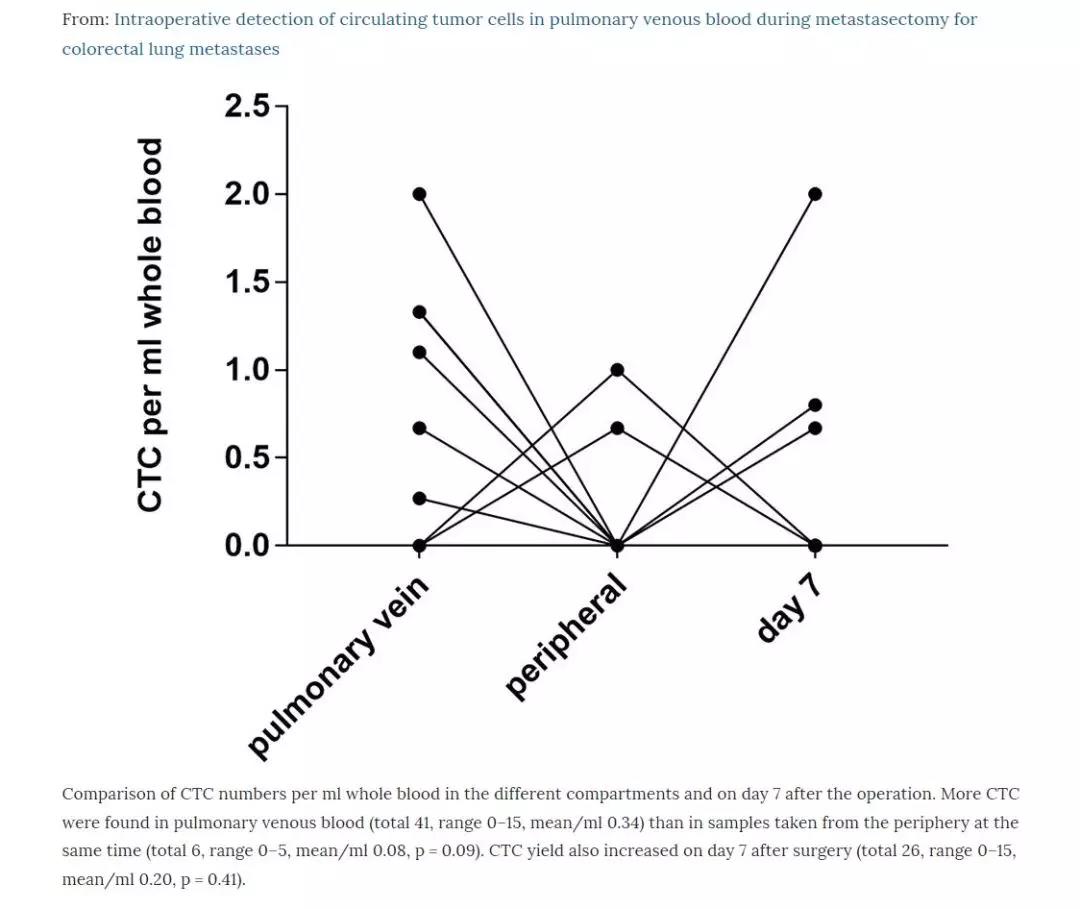

他们在24个结直肠癌肺转移瘤切除手术中,采集了转移癌病侧肺静脉血液。他们采用CellSieve-microfilters技术、免疫组织化学和Giemsa染色,对22个标本进行了枚举CTC检测。另外10个血液标本采用CellSearch-System进行分析。他们从肺静脉中枚举到癌细胞数(总计41,在0-15个范围),远远超过同时在肢体血管采血检测到的癌细胞数(总计6个,在0-5个范围,P=0.009)。在所有检测到CTC病例中,研究人员发现,肺静脉血中的癌细胞与肺转移结直肠癌导致局部淋巴侵犯有显著相关性(P=0.006),也就是说结直肠癌肺转移,并发肺部淋巴结转移的病人,肺静脉内更容易筛查到癌细胞。

研究人员进一步发现,肺静脉里找到的癌细胞就是来自结直肠癌肺转移肿瘤,他们还证实从肿瘤流出血管中找到癌细胞,是一项代表病人预计后果很差的指标。

在一些结直肠癌肺转移的病人中,经过严格筛选,一些病人接受了肺转移瘤切除术,术后5年生存率在40-70%之间,甚至有的病人达到治愈的结果。如果在术中抽取手术侧肺静脉血,并发现肿瘤细胞,这就预示病人术后预后不好,因为从肺转移肿瘤上脱落的癌细胞进入血液,会播散到全身其他部位,造成新的转移肿瘤。另外,肺转移肿瘤已经发生淋巴结转移的病人,肺静脉血中发现CTC,预示着病人的预后更差。

这项研究,证实了第二个假设,从转移肿瘤输出血管采血,分离出癌细胞的可能性更高,而从体循环(肢体血液)采血,CTC的发现率就没有那么高了。